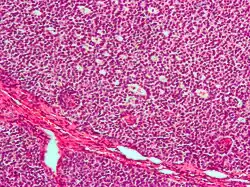

![]() | |

| Micrograph of a granulosa cell tumour, a type of sex-cord–gonadal stromal tumour. H&E stain. | |